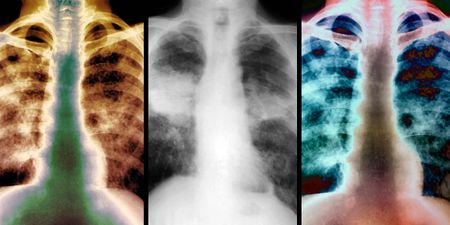

OCCUPATIONAL DISEASE Silicosis and lessons from ‘enormous suffering’ – how a ‘measure of social justice’ was gained for mineworkers 9 min 1 By Takudzwa Pongweni